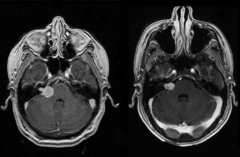

位于生命中枢的巨大脑干海绵状

海绵状血管瘤 在人群中少见,脑干(包括中脑、脑桥、延髓...